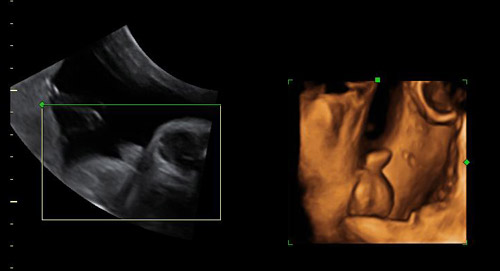

Ecografía 2D y 3D de genitales masculinos en el tercer trimestre de embarazo

Las imágenes muestran los genitales masculinos externos en ecografía de un embarazo avanzado. La ecografía en tres dimensiones, a la derecha, es más nítida: se ven las piernas levantadas y el aparato genital.